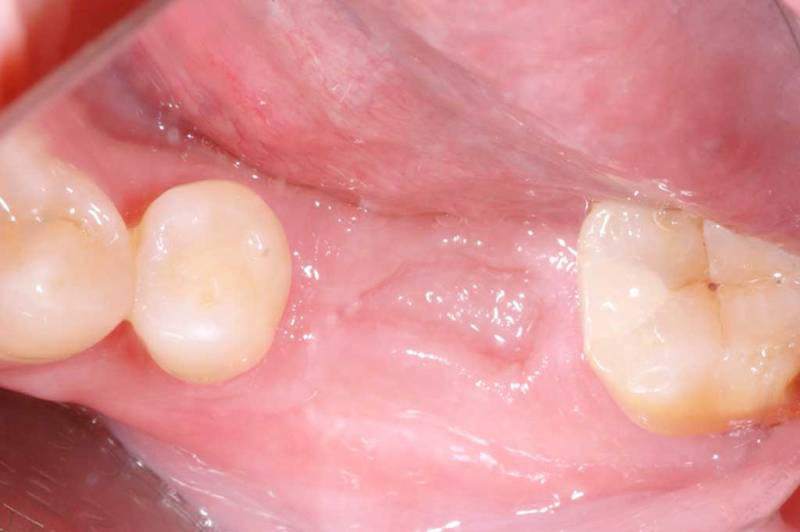

微創植牙術前

微創植牙術中

微創植牙術後